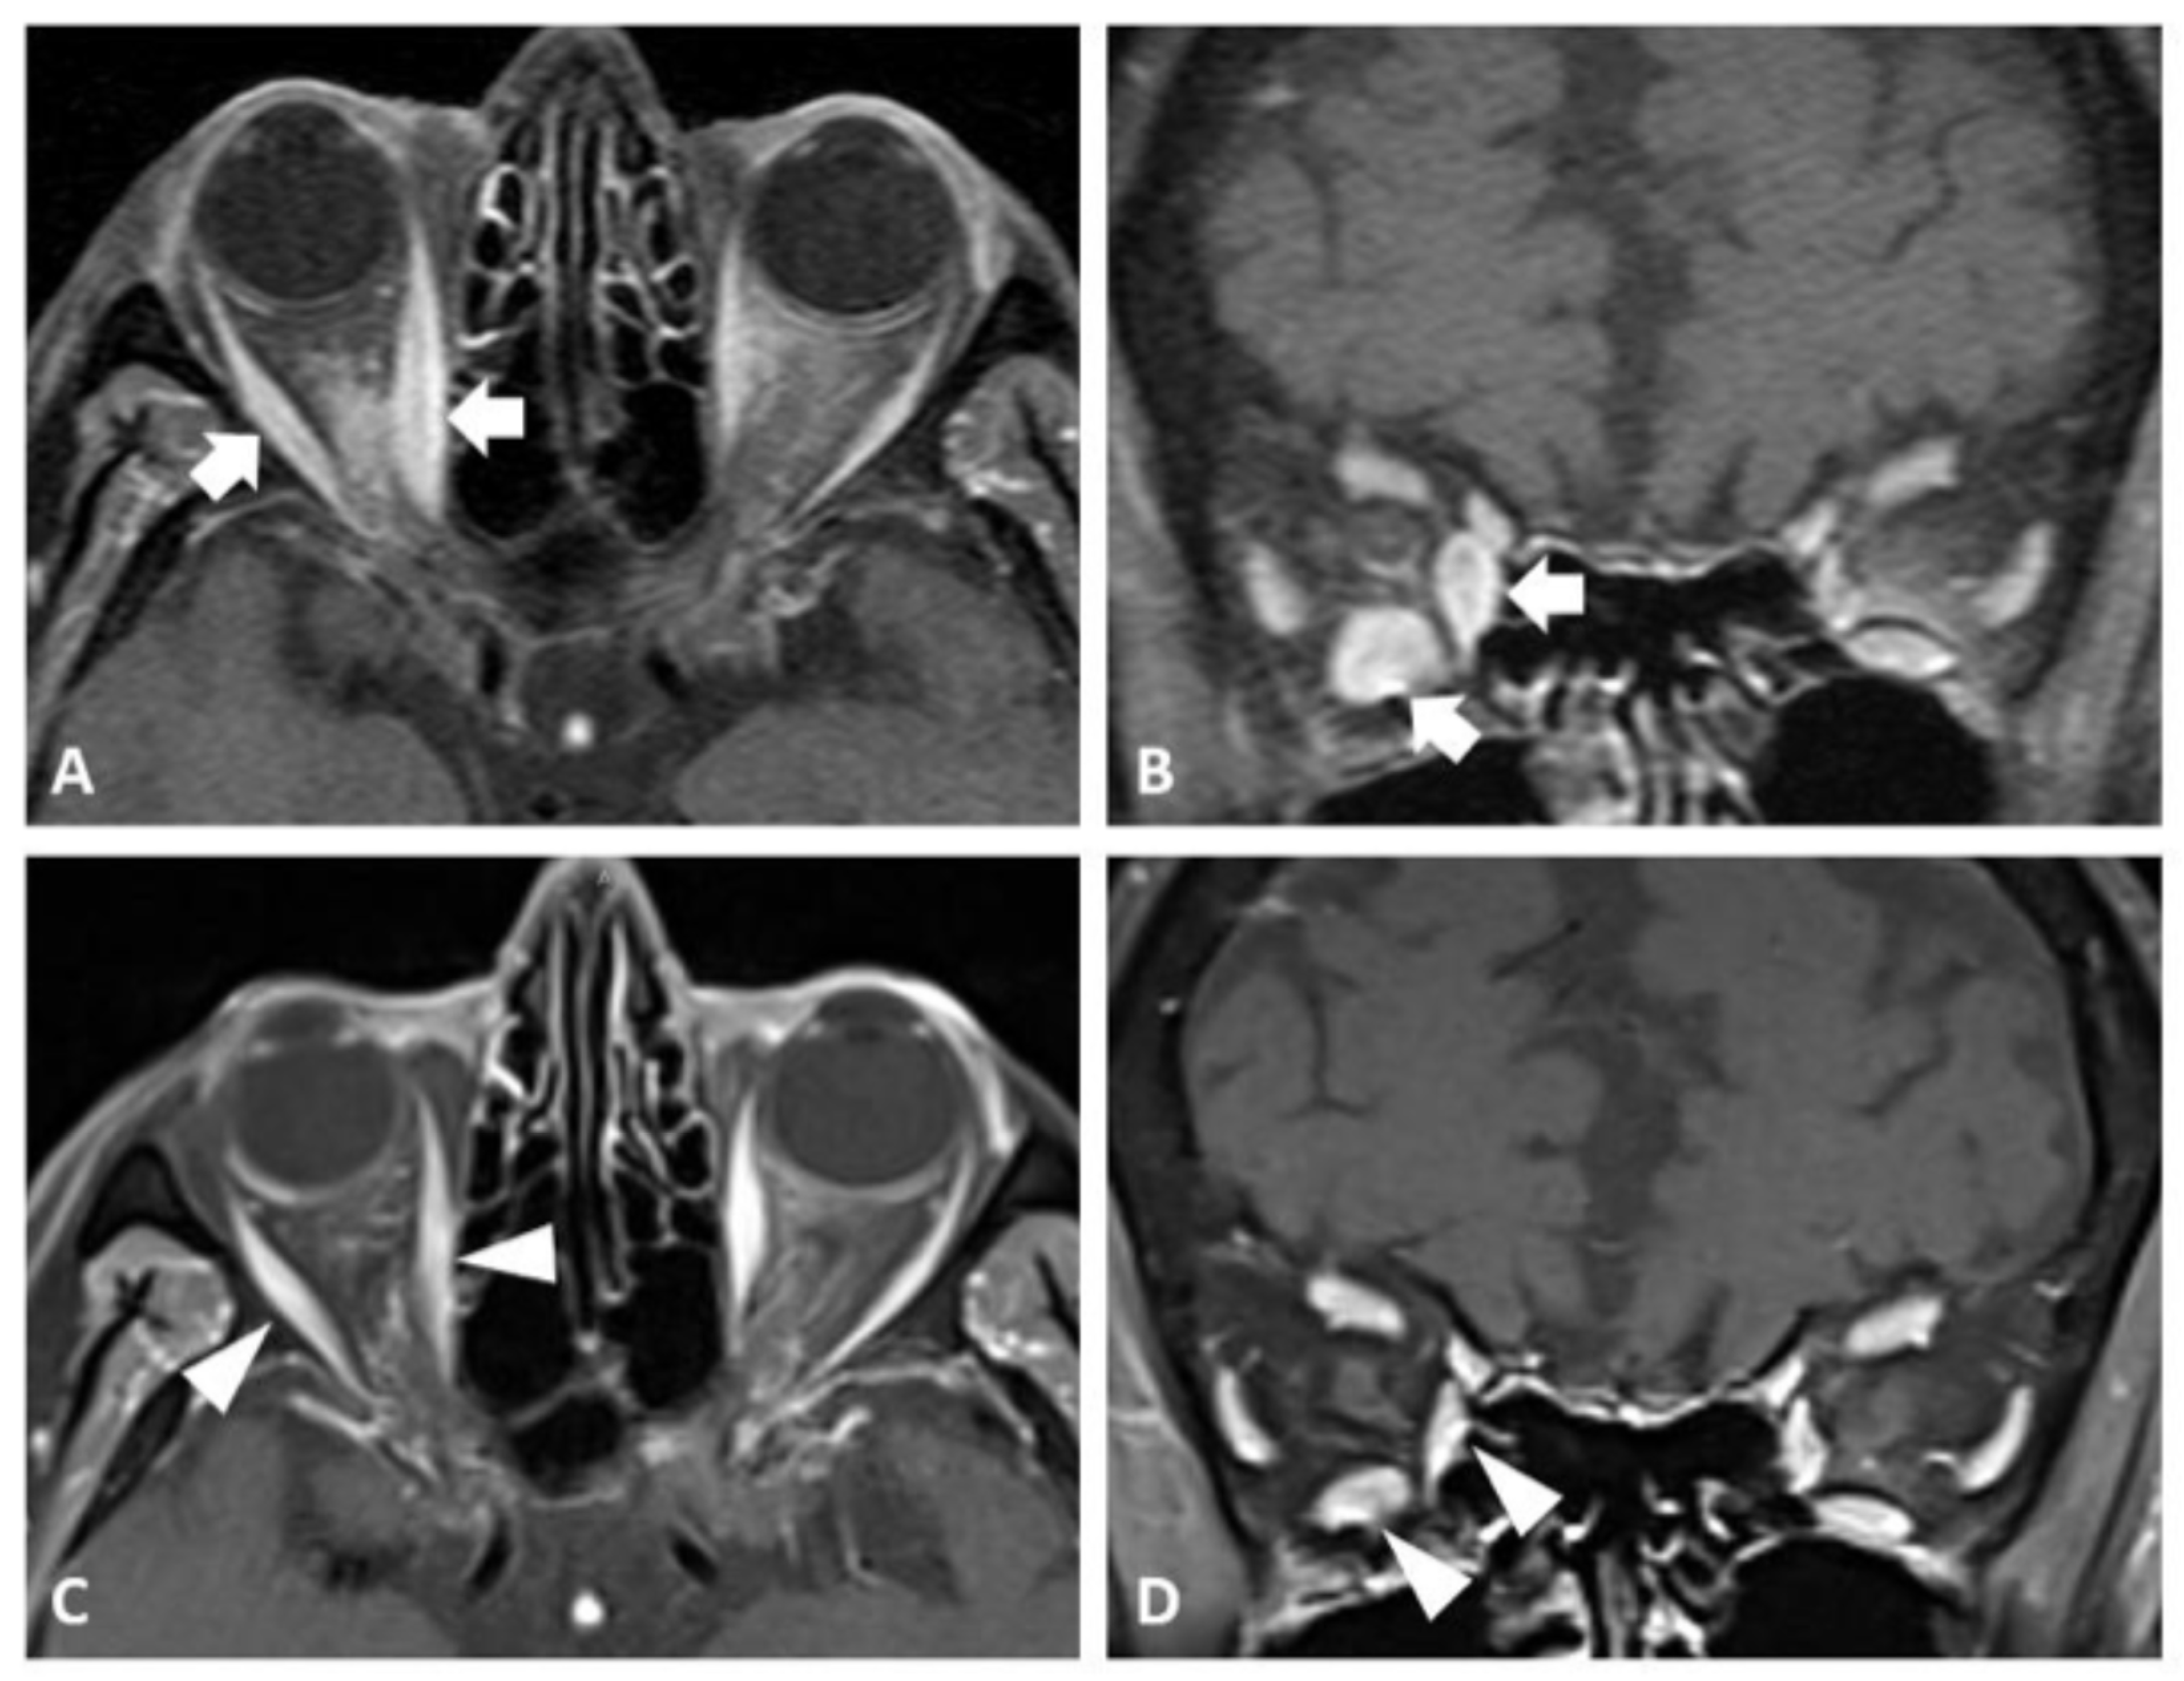

2.1. Case 1

2.2. Case 2